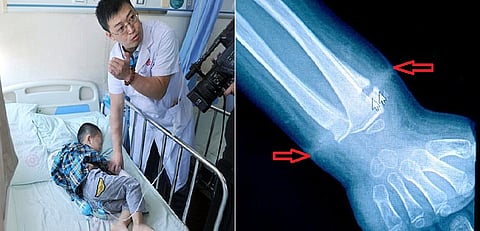

تمكّن أطباء من إزالة شريط مطاطي من على معصم صبي صيني، بعد أن كان ينمو داخل جلده لسنوات عدة.

وحسب موقع "سكاي نيوز عربية"، كان الطفل على وشك إجراء عملية جراحية لبتر يده من الرسغ، بعد أن اكتشف الأطباء في مستشفى تشانغدو في الصين حالته التي تؤثر في نمو العظام لدى الطفل.

وقال الأطباء إن الجسم الغريب حول معصم الطفل يؤثر في نمو عظام الصبي ويقيد حركة ذراعه.

وكان الأطباء على وشك إجراء عملية جراحية للطفل لبتر يده، إلا أنهم عثروا على الشريط المطاطي حول معصم الطفل مزروع داخل الجلد.